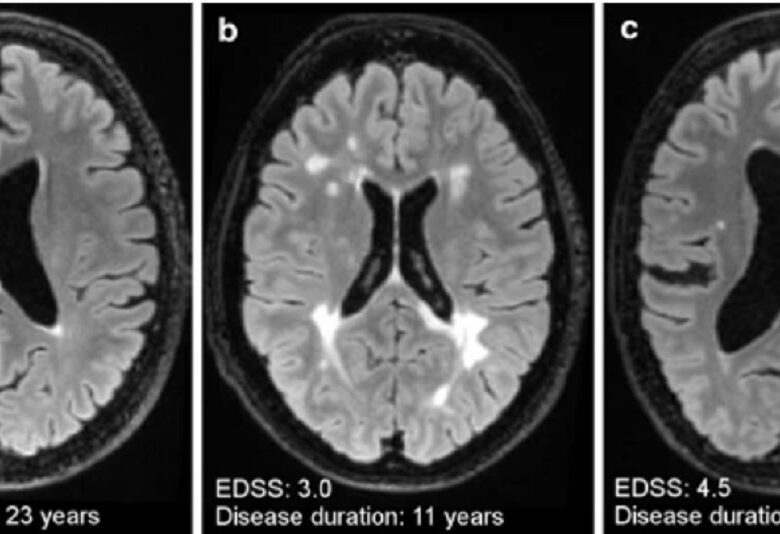

TIPURILE DE SCLEROZĂ MULTIPLĂ Fiecare persoană diagnosticată cu scleroză multiplă (SM) are propria poveste. Experiența la nivel individual este unică, în parte datorită multitudinii de simptome care se pot asocia în